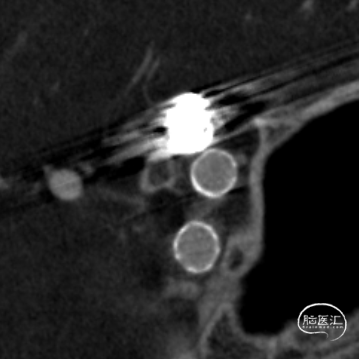

标记测量动脉瘤最大径6.2mm,动脉瘤颈4.2mm;近端血管直径4.4mm,远端3.6mm,后交通至海绵窦水平段长度约25mm。血流导向密网装置型号Surpass Evolve 4.5mm×25mm。

长鞘加持中间导管顺利到达预定位置。

微导管塑形后填入两枚弹簧圈。填塞第二枚弹簧圈时将第一个弹簧圈的攀顶出一小段。

撤出微导管,XT-27送至大脑中动脉。

Surpass Evolve血流导向密网装置远端着陆点位于脉前动脉近端。

Surpass Evolve血流导向密网装置释放至可回收点。

造影提示脉前动脉与后交通动脉之间血管有一定角度,装置远端贴壁不理想。

远端贴壁不良

回收顺畅

再释放,远端开放、过弯开放的性能好。

造影证实Surpass Evolve血流导向密网装置远端开放好。

远端贴壁良好。

完全释放Surpass Evolve血流导向密网装置。

动脉瘤大部分栓塞,局部造影剂滞留。

稀释造影剂DYNA CT提示:血流导向密网装置开放、贴壁良好。